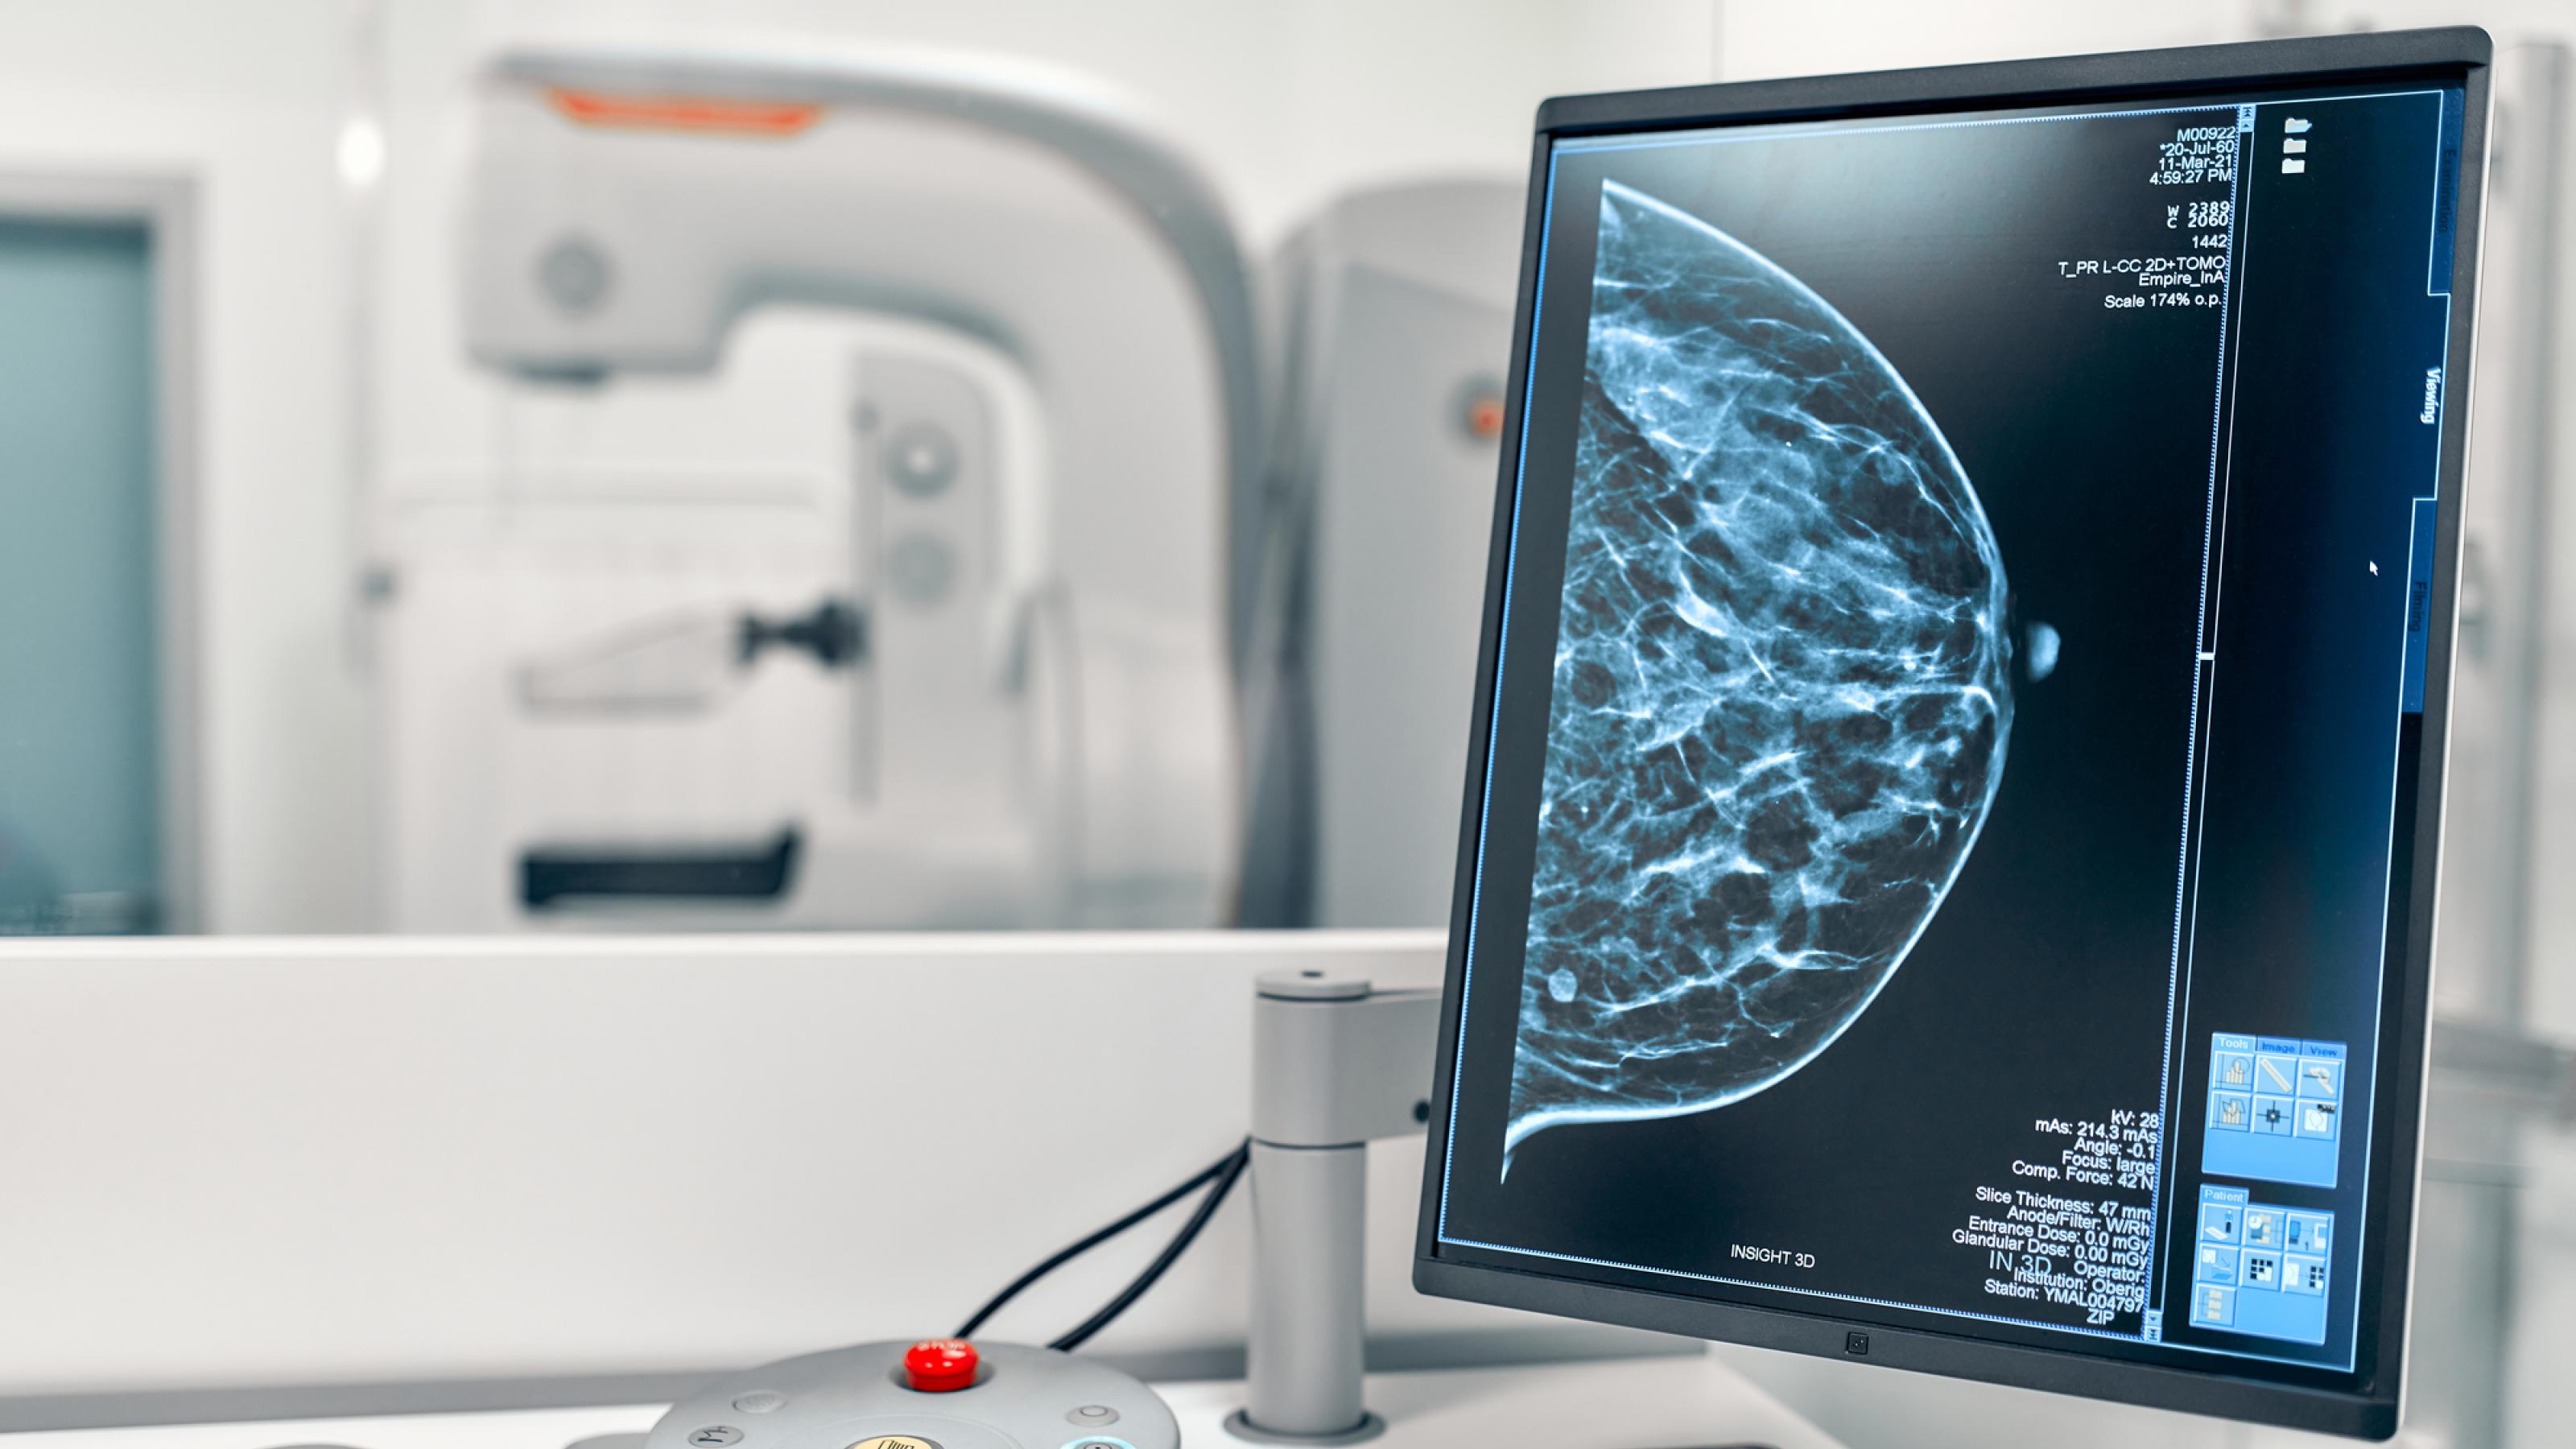

Seit Einführung der Röntgen-Reihenuntersuchung auf Brustkrebs, genannt Mammographie-Screening, diskutieren Expertinnen und Experten darüber, ab welchem Alter und bis zu welchem Alter das Screening angeboten werden soll. Konsens ist das Kernalter von 50 bis 69. So werden auch in Deutschland seit knapp 20 Jahren Frauen in diesem Alter in einem organisierten Programm alle zwei Jahre eingeladen, ihre Brust röntgen zu lassen. Nun ist es beschlossene Sache, dass sie ab Juli 2024 weitere fünf Jahre am Screening-Programm teilnehmen können. Obwohl etliche Gremien die Studienlage intensiv geprüft haben und die Ausweitung empfehlen, wettern Fachleute um den ehemaligen Max-Planck-Direktor Gerd Gigerenzer gegen den Beschluss. Ihrer Ansicht nach rettet das Mammographie-Screening kein Leben. Der Streit ist ein Lehrbuchbeispiel dafür, wie Wissenschaft funktioniert.